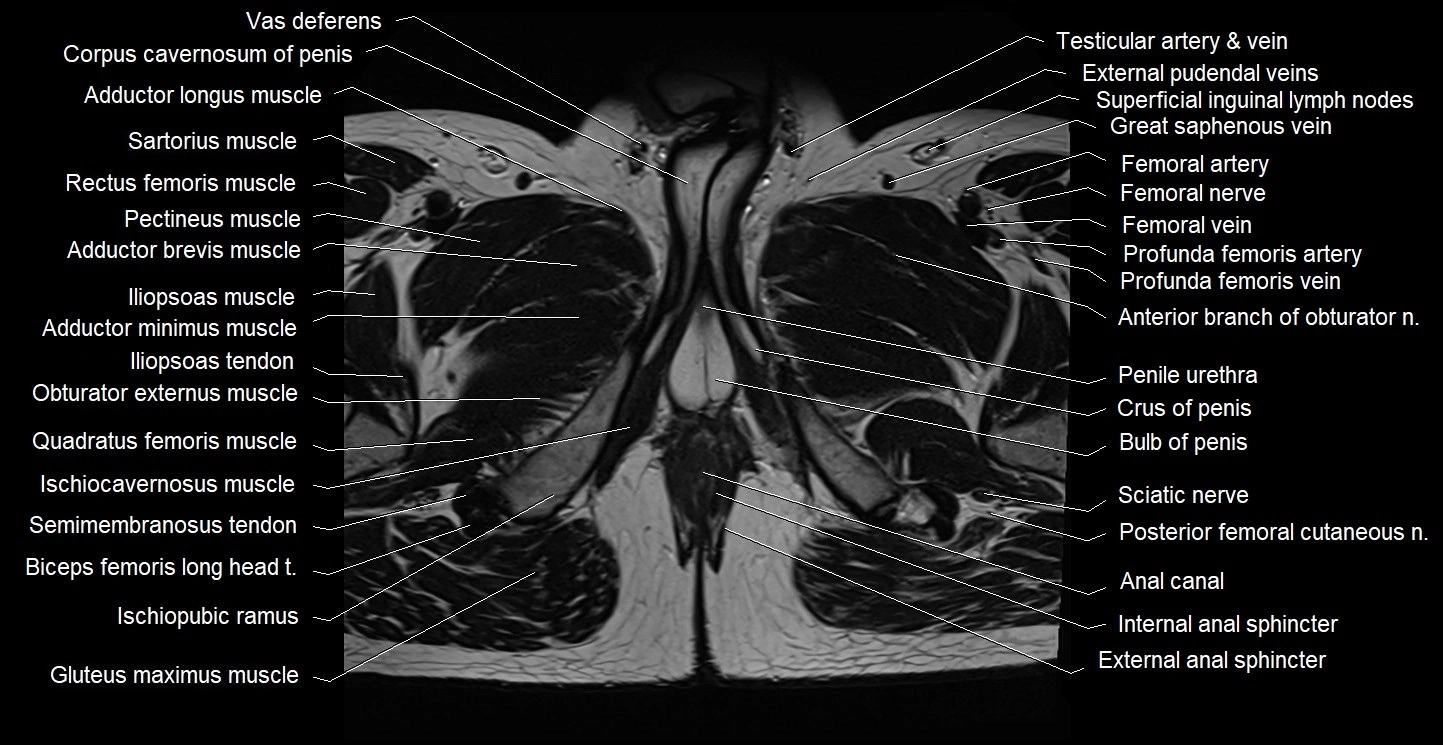

- Anal canal

- Bulb of Penis

- Crus of penis

- External anal sphincter

- Internal anal sphincter

- Ischiocavernosus muscle (Male)

- Ischiopubic ramus

- Penile urethra

- Posterior femoral cutaneous nerve

- Sciatic nerve